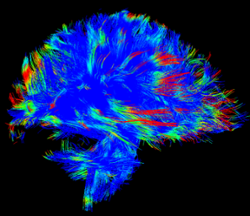

Baron, Parraga, and Paul named CRCs

Western News , June 17, 2019

Faculty members Corey Baron and Grace Parraga, and incoming faculty member Arghya Paul have been named Canada Research Chairs in the latest round announced by Kirsty Duncan, Minister of Science and Sport.